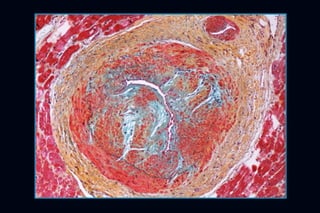

ISQUEMIA MIOCÁRDICA

─   Generalmente no relacionada con CAD

─   Mismatch entre oferta-demanda

─   Aumento de demanda por HVI

─   Compromiso de Q coronario

─   (hipertrofia de la media, arterias intramurales)

─   Inducir arritmias y MS

─   Hasta 40% de isquemia detectada por Medicina Nuclear

ISQUEMIA MIOCÁRDICA ─ Generalmente no relacionada con CAD ─ Mismatch entre oferta-demanda ─ Aumento de demanda por HVI ─ Compromiso de Q coronario ─ (hipertrofia de la media, arterias intramurales) ─ Inducir arritmias y MS ─ Hasta 40% de isquemia detectada por Medicina Nuclear

• #20 Pathology of hypertrophic cardiomyopathy A. Post-mortem examination of the heart from an individual ith HCM demonstrating massive asymmetric left ventricular hypertrophy, with associated reduction in left ventricular cavity size, compared to a normal heart. B. Histopathology of heart sections stained with Massons trichrome showing significant myofibre disarray and interstitial fibrosis in HCM.

• #21 Small Intramural Dysplastic Coronary Arteriole

• #22 Small intramural coronary artery shows a narrowed lumen due to disordered smooth muscle hyperplasia in the intima and media. There is increased deposition of mucopolysaccharide (blue green) in the intima and collagen (yellow) in the adventitia.